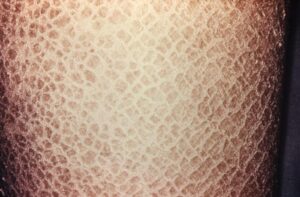

يشير السماك إلى مجموعة من الاضطرابات الجلدية. يؤدي إلى جفاف وحكة الجلد الذي يبدو متقشرًا وخشنًا وأحمر اللون. يمكن أن تتراوح الأعراض من خفيفة إلى شديدة. يمكن أن يؤثر السماك على الجلد فقط، ولكن في بعض الأحيان يمكن أن يؤثر المرض على الأعضاء الداخلية أيضًا.

يشير السماك إلى مجموعة من الاضطرابات الجلدية التي تؤدي إلى جفاف الجلد وحكةه والذي يبدو متقشرًا وخشنًا وأحمر. يمكن أن تتراوح الأعراض من خفيفة إلى شديدة. يمكن أن يؤثر السماك على الجلد فقط، ولكن بعض أشكال المرض يمكن أن تؤثر على الأعضاء الداخلية أيضًا.

- قشور على الجلد بيضاء أو رمادية أو بنية ولها المظهر التالي:

- صغيرة وقشاري.

- قشور كبيرة داكنة تشبه الصفيحة.

- حراشف صلبة تشبه الدروع.